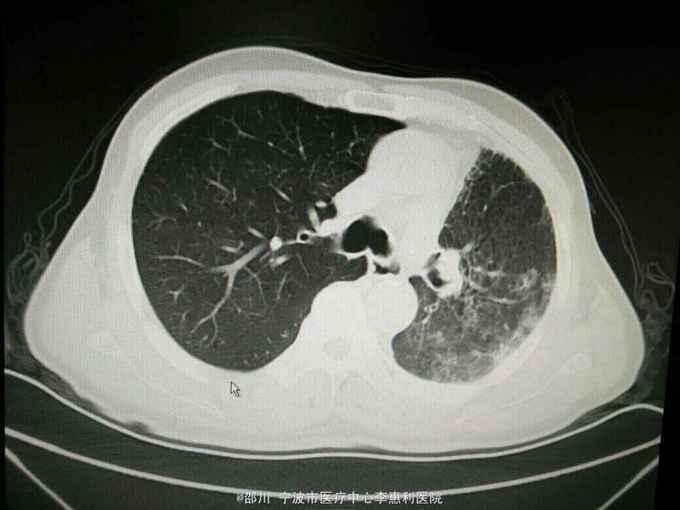

查体:神志清,精神好,生命体征平稳。两肺呼吸音清,未闻及干湿啰音。 辅查:血常规:WBC 9.0×10^9/L,NE 65.1%, Hb 152g/L, plt 246×10^9/L。血CEA 41.6ug/L。小便常规,大便常规,凝血功能,D-二聚体,肝肾功能,电解质均无明显异常。心电图,腹部B超无异常。 2015-10-30我院胸部CT见下图。